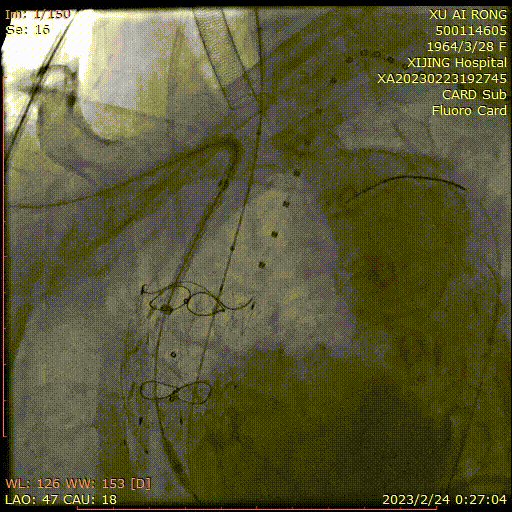

★ 病例4

王某,女,56岁,“突发胸背痛15小时”入院,主动脉CTA提示:升主动脉-腹主动脉管腔外可见新月形低密度影,主动脉弓前部可见溃疡,大小约0.6cm。

术前CTA

术前造影

术后造影

手术用时 95分钟